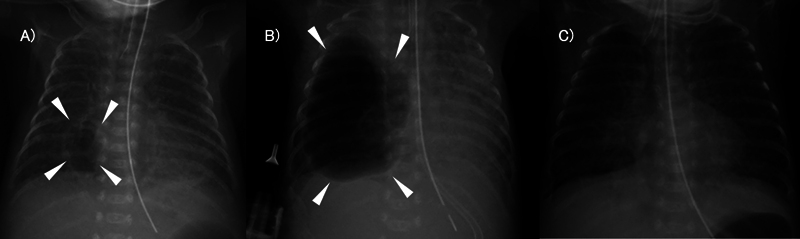

Giant pulmonary cyst in extremely low birth weight (ELBW) infants has been described as one of severe pulmonary diseases. Any definitive therapy for refractory cases, where conservative methods of treatments are not effective, has not been established as a standard. Herein, we report an ELBW infant with a giant pulmonary cyst cured by percutaneous drainage without any adverse events. A female infant was born with a birth weight of 327 g. Surfactant was administered on days 1 and 2 of life to treat respiratory distress syndrome. Tracheal intubation was performed and synchronized intermittent mandatory ventilation was promptly initiated following birth. On the course, right giant pulmonary cyst developed on day 9 after birth. Although we started conservative therapy, including right lateral decubitus positioning, high-frequency oscillatory ventilation, and systemic corticosteroid administration, the diameter of the cyst had reached 34 mm, and mediastinal displacement was observed on day 28 after birth when she weighed 393 g. She recovered by percutaneous drainage followed by suction with a pressure of -10 cm H 2 O under mild sedation for 3 days. We believe that percutaneous drainage can be one of the available options for unilateral pulmonary interstitial emphysema.